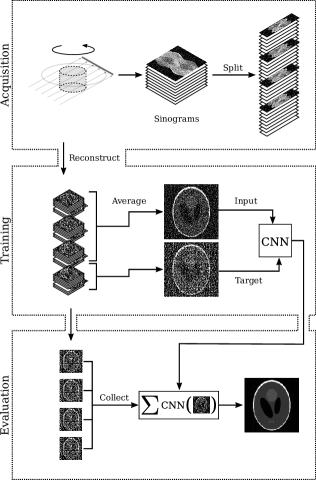

Refer to caption

Figure 2: Noise2Inverse for computed tomography. First, 3D parallel-beam tomography obtains a stack of noisy sinograms by integrating over parallel lines at several angles. Next, the stack of sinograms is split along the angular axis. Then, the split sinograms are reconstructed to act as training dataset. During training, a dynamic subset of slices is averaged to form the input; the target is the average of the remaining slices. To obtain a low-noise result, the trained CNN is applied to all arrangements of input slices and averaged.

In this section, we describe our implementation of Noise2Inverse for 3D parallel-beam tomography, and discuss how the implementation relates to the theoretical considerations discussed before.

The 3D parallel-beam tomography problem may be considered as a stack of 2D parallel-beam problems. In 2D parallel-beam tomography, a parallel X-ray beam penetrates an object, after which it is measured on a line detector. The line detector rotates around the object while capturing the intensity of the attenuated X-ray beam, as illustrated in the top panel of Figure 2.